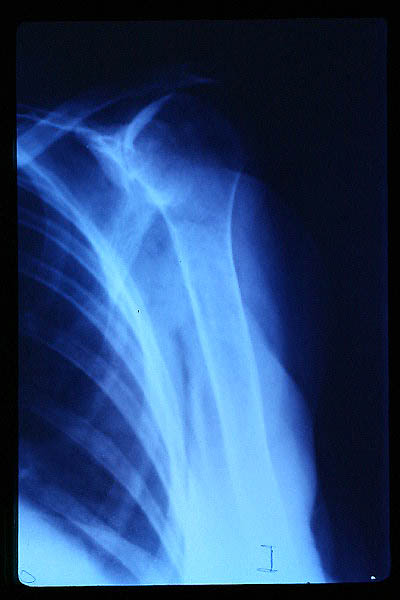

APR Luxación de hombro

Fractura de húmero, intensa desviación de fragmentos